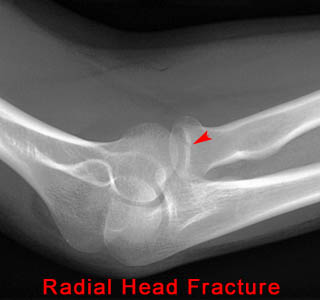

13) Name the abnormality shown in the image below.

14) What other clinical finding(s) would you expect to find in a patient with the fracture shown above?

Soft Tissue Abnormalities